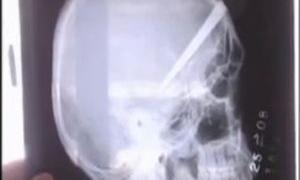

Бразилієць жив з лезом ножа в голові протягом трьох років

28 вересня 2010, 18:19

Хірурги з клініки бразильської клініки витягнули лезо довжиною 6 см з голови 29-річного пацієнта.